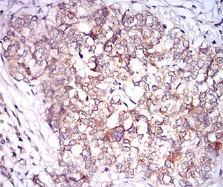

IHC    1/100 - 1/500